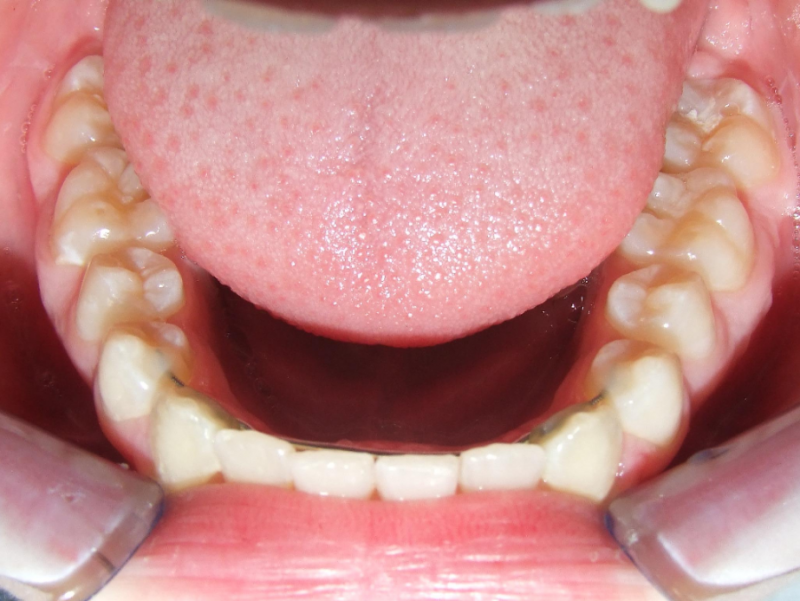

Behandeling Raoul

Duur

van 13-3-14 tot 16-9-15

Beschrijving

Leeftijd bij aanvang: 10 jaar

Bonded Hyrax + volledig vast onderkaak

Volledig vast bovenkaak + expander

Wrap + c-c bar onderkaak

Leeftijd bij afname: 12 jaar

Voor behandeling

Na behandeling